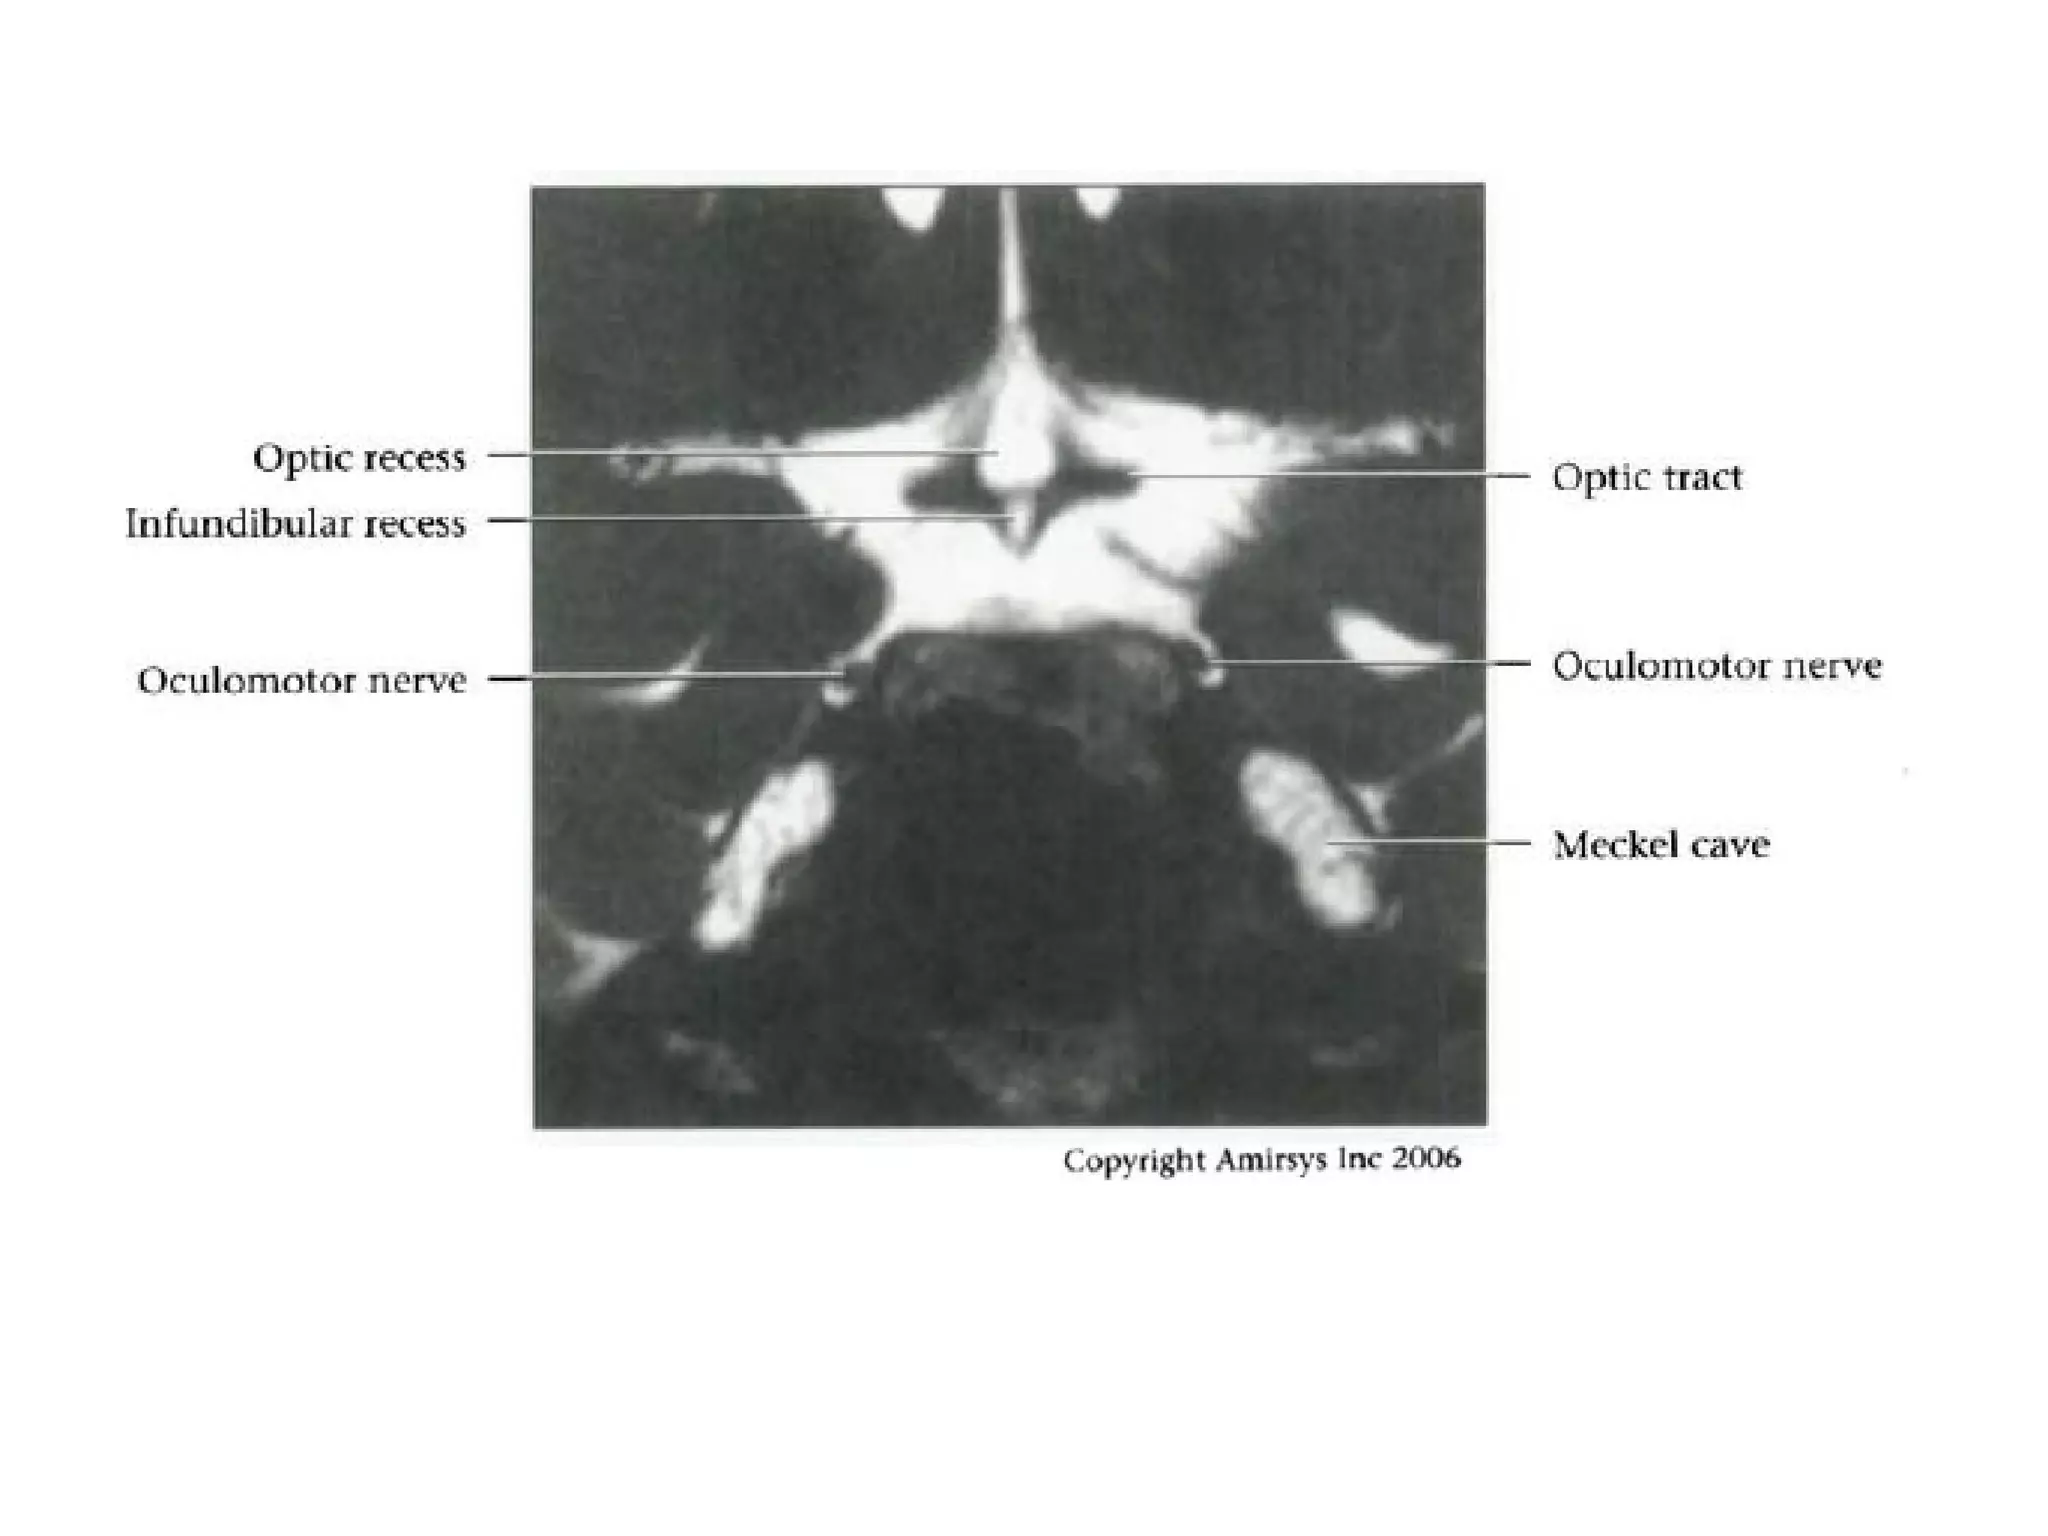

Cranial Nerve III:

The Oculomotor Nerve

• The oculomotor nerve originates from nuclei deep to the

superior colliculus, ventral to the cerebral aqueduct, and

inferior to the pineal gland.

• The nerve then travels across the midbrain from

posterior to anterior.

• The oculomotor nerve root emerges into the

interpeduncular cistern, and this root entry zone in the

cistern is a good way to identify the oculomotor nerve on

axial SSFP MR images.

• In the prepontine cistern, the nerve travels between the

superior cerebellar and posterior cerebral arteries, which

makes it easy to identify on coronal SSFP images.

RadioGraphics 2009; 29:1045–1055

• The cavernous segment of the oculomotor nerve

runs along the lateral wall of the cavernous sinus

and is the most superior of the nerves in this

sinus.

• The oculomotor nerve then enters the orbit

through the superior orbital fissure, before

splitting into superior and inferior divisions lateral

to the optic nerve.

• Knowledge of this anatomy may be helpful for

identifying the precise location of a nerve

abnormality.